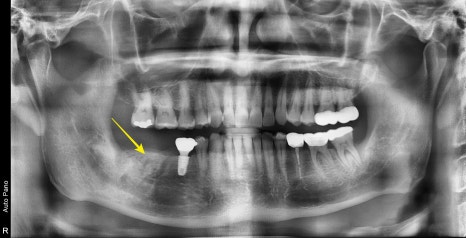

약 3달후 수술 부위 주변골을 평가했습니다.

다행히 뼈가 잘 회복이 되어 임플란트를 식립하기 좋은 조건이 되었습니다.

노란색으로 표시된 부분이 골 이식재가 단단해져 좋은 환경을 제공해 주었습니다.

아직은 뼈가 단단하진 않기 때문에 좋은위치에 식립한 후

임플란트와 뼈가 더 단단하게 결합되도록 2달 정도 기다렸습니다.